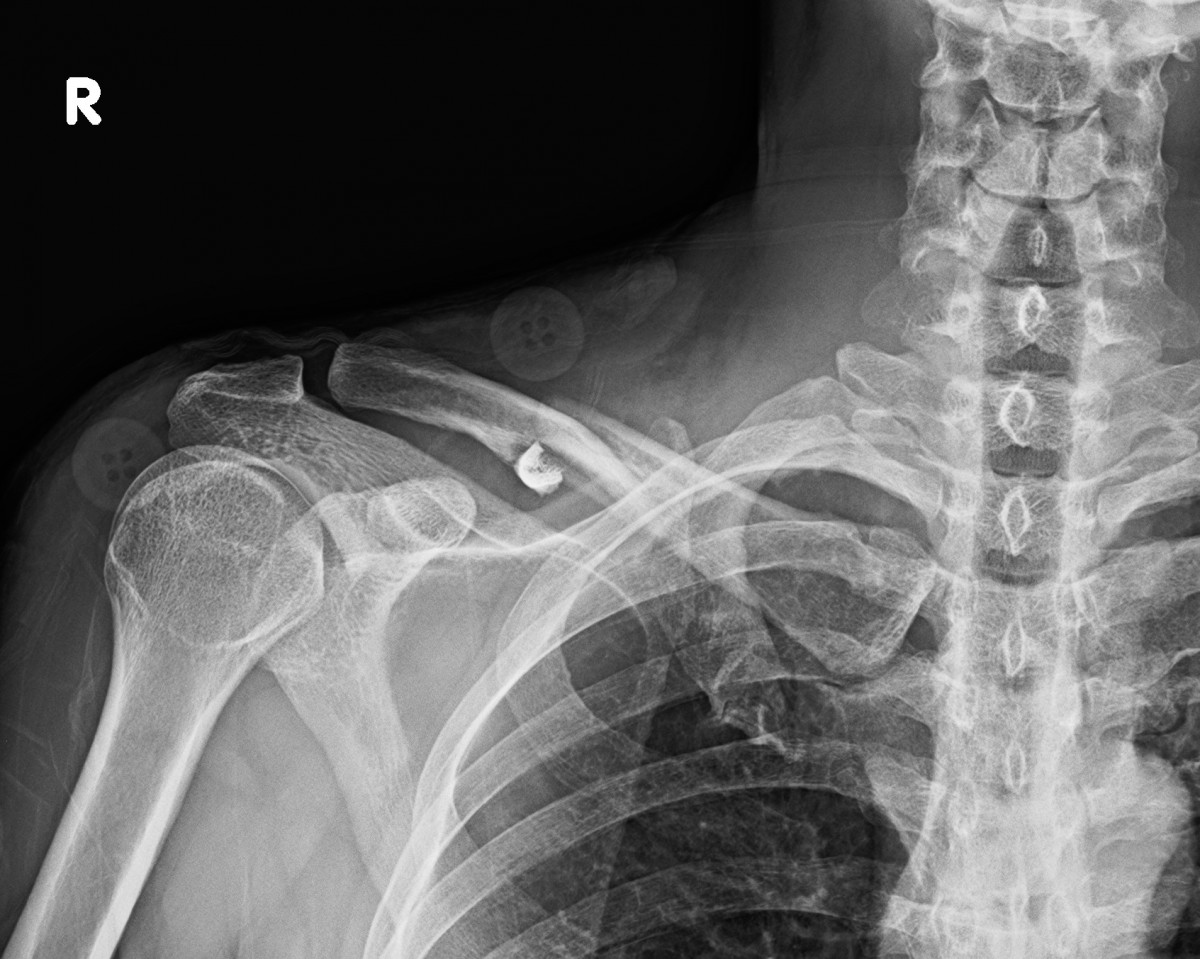

이재상원장님 어깨 골절 수술 곽평O 환자

dae765e4d9ac96aee867c9d6292d8784_1758002837_8587.jpg